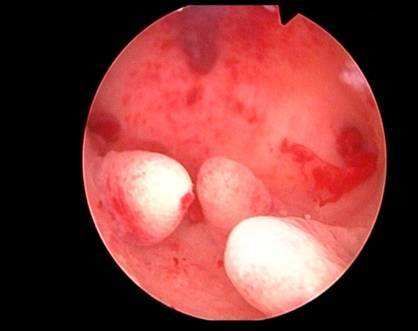

张某(子宫内膜癌)。37岁,肥胖,已婚,生育2孩。因“月经量增多伴经行间延长1年”就诊。既往在当地医院就诊,多次B超均提示子宫内膜增厚,予中西医治疗后,效果不佳,转诊我科。行B超检查提示:子宫内膜过厚,与肌壁边界不清。建议患者行宫腔镜手术,术中见子宫内膜肥厚,表面血管丰富。术后病检报:子宫内膜癌。接着行“子宫内膜癌根治术”,术后病捡提示:子宫内膜癌,无淋巴结转移。术后患者病愈出院。